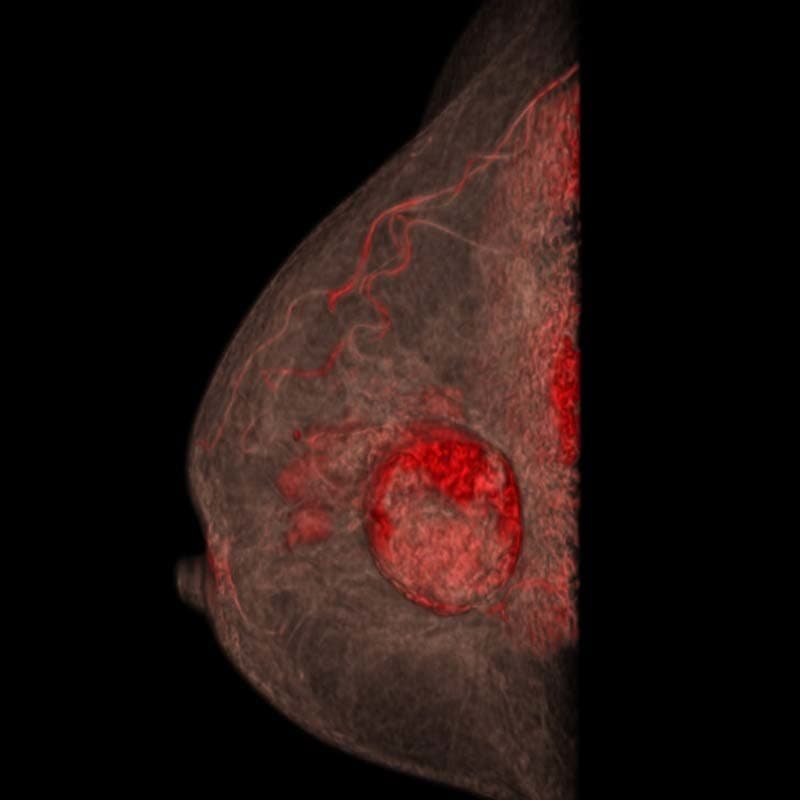

多発性乳がん

患者背景

• 70~79歳の女性で、右乳房に触知可能な腫瘤を認める。

• 過去のマンモグラフィでは単一の腫瘤のみが描出されていた。

• 超音波検査では、病変は円形かつ境界明瞭で、嚢胞性と固形成分を伴っていた。さらに、滑らかで不規則な辺縁を有する複数の低エコー性病変が検出された。

多発性乳がんの疑いを確認するため、乳腺CT検査を実施した。

画像詳細

• 造影前:円形の腫瘤性病変で、中心部に低吸収(壊死/液体)領域を認める。画像所見は複数の病変を疑わせる。

• 造影後:触知可能な腫瘤は造影剤を不均一に増強します。乳房の複数の象限に、不規則な縁と滑らかな縁を有する複数の造影増強腫瘤が明示されています。

評価:BI-RADS 5

画像提供:エヴリン・ヴェンケル医学博士(エルランゲン大学病院)

多発性乳がん画像